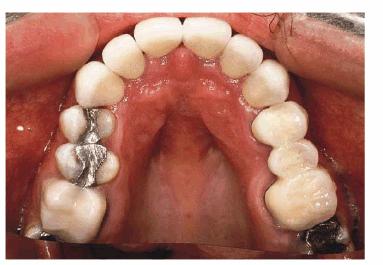

access to the preparation margins. Six full porcelain crowns restored the

esthetics of the maxillary arch (Figure 24-7G), whereas composite resin bonding helped restore

mandibular esthetics. A maxillary occlusal night appliance was constructed for

the patient to wear since the patient had a history of clenching while

sleeping.

Figure 24-7G: The final six crowns show improved proportion and symmetry in the arch.

RESULT: The resulting smile with straighter and lighter teeth (Figures 24-7H, and 24-7I) was most appreciated by the patient.

Figure 24-7H: Pretreatment smile.

Figure 24-7I: Post-treatment smile with six maxillary full porcelain crowns and four mandibular incisors with bonded composite resins.